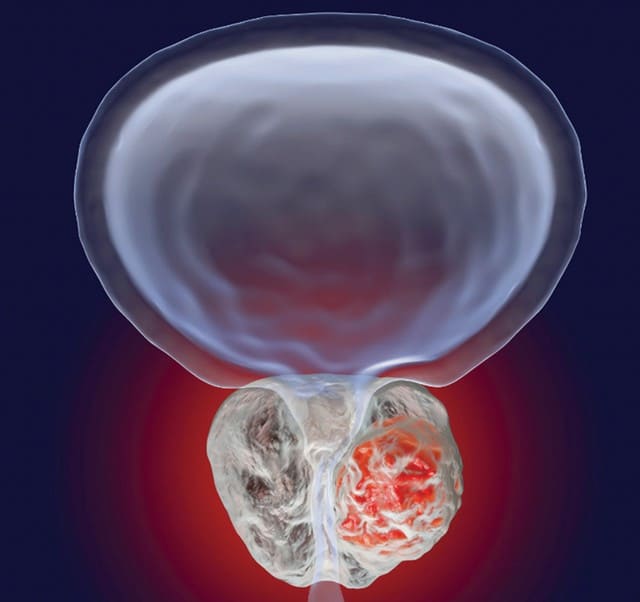

Aparecen células cancerosas

Debido a que la glándula está constantemente inflamada, en ella aparecen y crecen células cancerosas. Esto lleva primero al adenoma de próstata, y luego al cáncer. El cáncer de próstata es incurable. Normalmente se detecta solo en fase terminal. Y a los hombres solo les quedan unos meses de vida. El cáncer de próstata se considera el tipo de oncología más peligroso y vergonzoso.

Así se ve el cáncer de próstata.